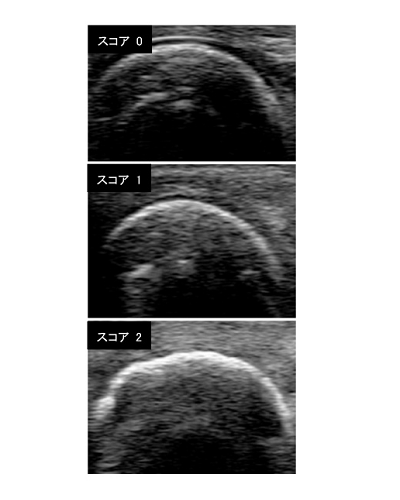

研究グループは、2011~2015年に東邦大学医療センター大橋病院膠原病リウマチ科を受診した関節リウマチ患者103人と健常対照者42人を対象として、両手第2~第5指の近位指節間関節と中手指節間関節の計16関節の軟骨厚を関節超音波によって計測。さらに軟骨損傷の度合いを関節超音波による簡便な3段階の半定量法(関節毎のスコアが0~2、評価16関節の合計0~32)で評価した。

その結果、健常対照者と比較して関節リウマチ患者では有意に軟骨厚が減少し、軟骨損傷の半定量法スコアが、健常対照者が4点、関節リウマチ患者では2倍の8点(いずれも中央値)と高値であるとわかった。また、関節リウマチ患者においては、軟骨厚の計測値、軟骨損傷スコアのいずれもが、従来の軟骨損傷の推定法である関節X線における関節裂隙狭小化スコアと良好な相関を示した。さらに、関節リウマチに長く罹患しているほど軟骨損傷が進行することも判明した。

軟骨損傷の半定量法スコアはOMERACT(Outcome Measures in Rheumatology)という国際的な臨床評価法の検討組織から本年論文発表されたばかりの方法。「関節超音波検査は、従来用いられていた関節炎と骨損傷の評価のみならず、軟骨損傷の評価にも適しており、関節リウマチにおける関節病変の包括的評価が可能なツールであることを実証した」と、研究グループは述べている。